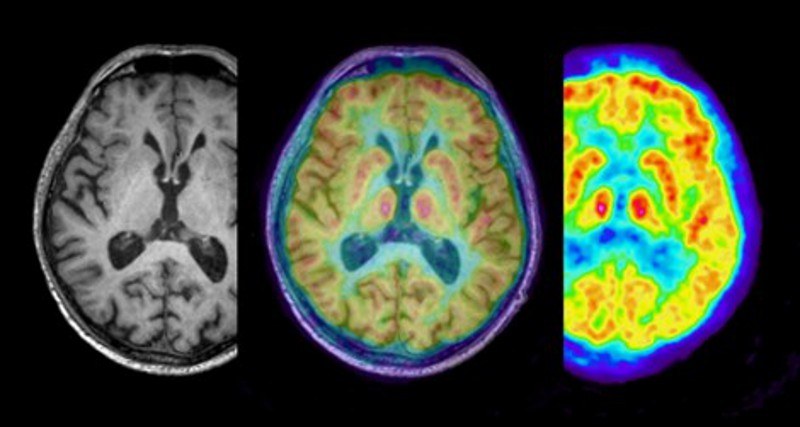

The research and development activities of the Medical Imaging Physics division (INM-4) of the Institute of Neuroscience and Medicine concentrate on the development, experimental validation and the clinical implementation of novel brain imaging methods. The focal points comprise the development of novel methods in the area of ultra-high field magnetic resonance imaging (MRI) and the development of hybrid imaging combining MRI with positron emission tomography (PET). Such combinations present unique opportunities for the simultaneous acquisition of structural changes, physiological and biochemical data and provide excellent perspectives for clinical applications to neurological diseases, e.g. for the diagnosis and therapy of brain tumours. In cooperation with our partner institutes, novel tracers for PET-MR imaging are investigated in animal experiments and validated by means of autoradiography, immunofluorescence imaging and histological methods.